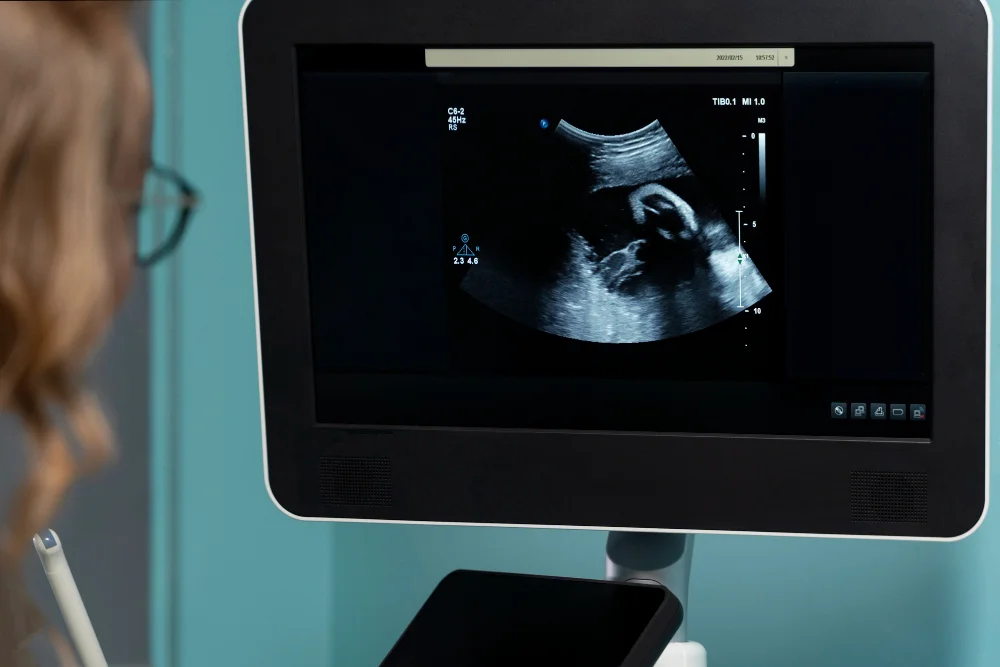

УЗИ брюшной полости в Харькове

УЗИ органов брюшной полости и заочеревинного пространства (почек) – диагностическая процедура, позволяющая определить размер и структуру паренхиматозных (плотных) органов живота и дать характеристику кровотока в крупных сосудах живота и внутриорганных сосудах. Ограничений по количеству и частоте проведения такого обследования нет, поэтому врач может назначать его и в качестве первичного скринингового обследования, и с целью динамического наблюдения за выявленными изменениями при ультразвуковом или томографическом исследовании. Структуры, которые можно обследовать с помощью комплексной диагностики органов брюшной полости, назначенной гастроэнтерологом:

Обследование позволяет

Информативность метода охватывает как экстренные состояния, так и хронические патологии. УЗИ органов брюшной полости покажет:

- наличие свободной жидкости или газа в брюшной полости;

- признаки внутреннего кровотечения;

- разрыв органов вследствие травм;

- хирургическую патологию: желчнокаменную болезнь, колики, панкреатит, нефролитиаз, воспалительные деструктивные процессы;

- диффузные и очаговые изменения, требующие уточнения с помощью томографии или биопсии.

Расшифровка УЗИ органов брюшной полости выполняется квалифицированным специалистом сразу после завершения процедуры или в течение нескольких часов в сложных случаях. Вид ультразвуковой диагностики является базовым этапом для принятия клинического решения. При необходимости может быть дополнен томографическим или лабораторным обследованием.